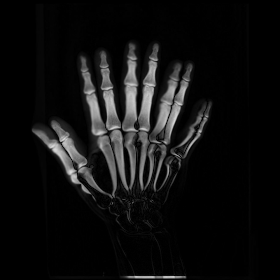

We then consider another example of registering two hand X-ray images with larger deformations (see Fig. 8(a) for the source image, Fig. 8(b) for the target image, and Fig. 8(c) for their absolute intensity difference). The warped image produced by our proposed method (Fig. 8(d)) again closely resembles the target image with the intensity difference significantly reduced (see Fig. 8(e)). Fig. 8(f) shows that the mapping is smooth and bijective. For comparison, note that LDDMM [5] fails to match the fingers (Fig. 8(g)). While DROP [18] is capable of registering the fingers (Fig. 8(h)), it distorts the boundary shape of the overall image (Fig. 8(i)).

Refer to caption

Figure 8. The second hand X-ray example.